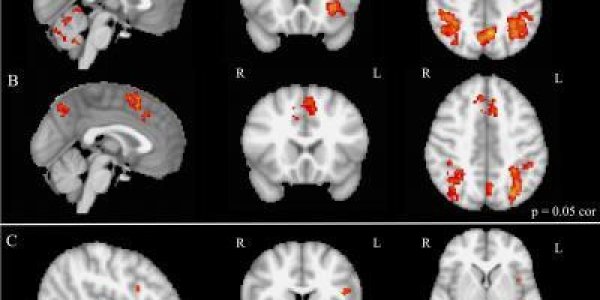

Why Music Boosts Memory - The Hippocampus

How do some people know the words to thousands and thousand of songs? A new study has found that the hippocampus, a brain structure crucial for creating long-lasting memories, is more active in…